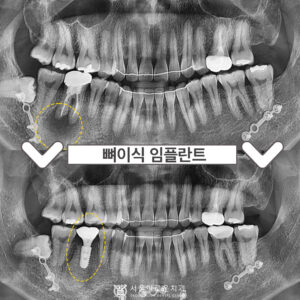

부천시청역치과 임플란트 뼈 이식이 필요하다면? 안녕하세요 😀 이로운 치료를 선사하는 서울이로운 치과입니다. ^^ 임플란트를 하고 싶어도 잇몸뼈가 충분하지 않아서 동네병원에서 하지 못하는 경우가 종종 발생하는데요. 오늘은 잇몸뼈가 없어서 임플란트를 할…